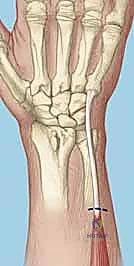

- Skin Incision: I'm making a longitudinal skin incision approximately 4-5 cm in length, centered directly over the third extensor compartment. This compartment houses the extensor pollicis longus (EPL) tendon. The incision should be roughly centered over Lister's tubercle, which you can palpate as a bony prominence on the dorsal aspect of the distal radius.

TECH FIG 1 • A. Axial image of dorsal wrist compartments with arrow indicating location for skin incision over third compartment. B. Skin incision centered over third dorsal compartment with superficial branch of the radial nerve (SBRN) and dorsal sensory branch of the ulnar nerve (DSBUN). Oval indicates tubercle of Lister. (Copyright © Mayo Clinic.)